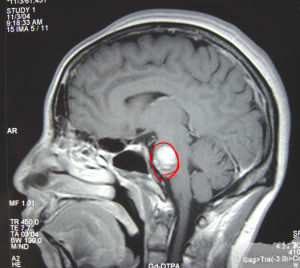

橋腦出血診斷

臨床表現為突然頭痛、嘔吐、眩暈、復視、眼球不同軸、側視麻痹、交叉性癱瘓或偏癱、四肢癱等。出血量少時,患者意識清楚可表現為一些典型的綜合徵,如foville綜合徵、millard-gubler綜合徵、閉鎖綜合徵等,可伴有高熱、大汗、應激性潰瘍、急性肺水腫、急性心肌缺血甚至心肌梗死。大量出血時血腫波及腦橋雙側基底和被蓋部,患者很快進如昏迷,雙側瞳孔呈針尖樣、側視麻痹、四肢癱瘓、呼吸困難、有去大腦強直發作,還可嘔吐咖啡色胃內容、出現中樞性高熱等中線症狀,常在48小時內死亡。